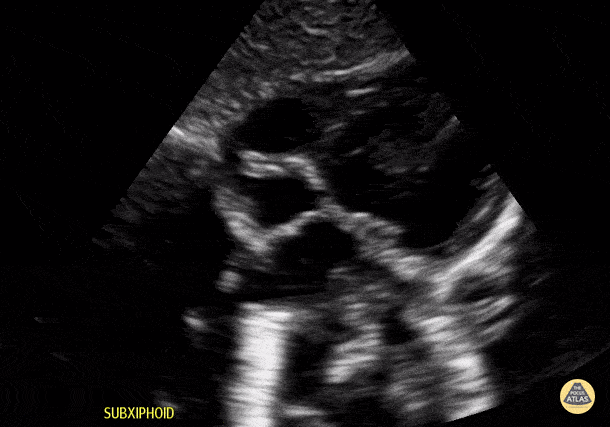

Normal Toddler Subcostal View. Contributor: Jaron Smith, MD, Phoenix Children's Hospital

View: Unspecified Parasternal Long Axis Parasternal Short Axis Apical Four-Chamber Subcostal Four-Chamber Subcostal Inferior Vena Cava Right Upper Quadrant Left Upper Quadrant Suprapubic Longitudinal Suprapubic Transverse Subxiphoid Anterior Thoracic Phrenic